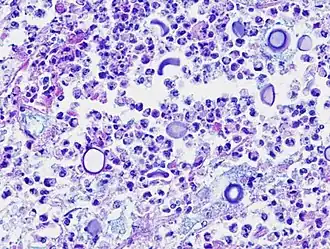

Микрофотография возбудителя заболевания